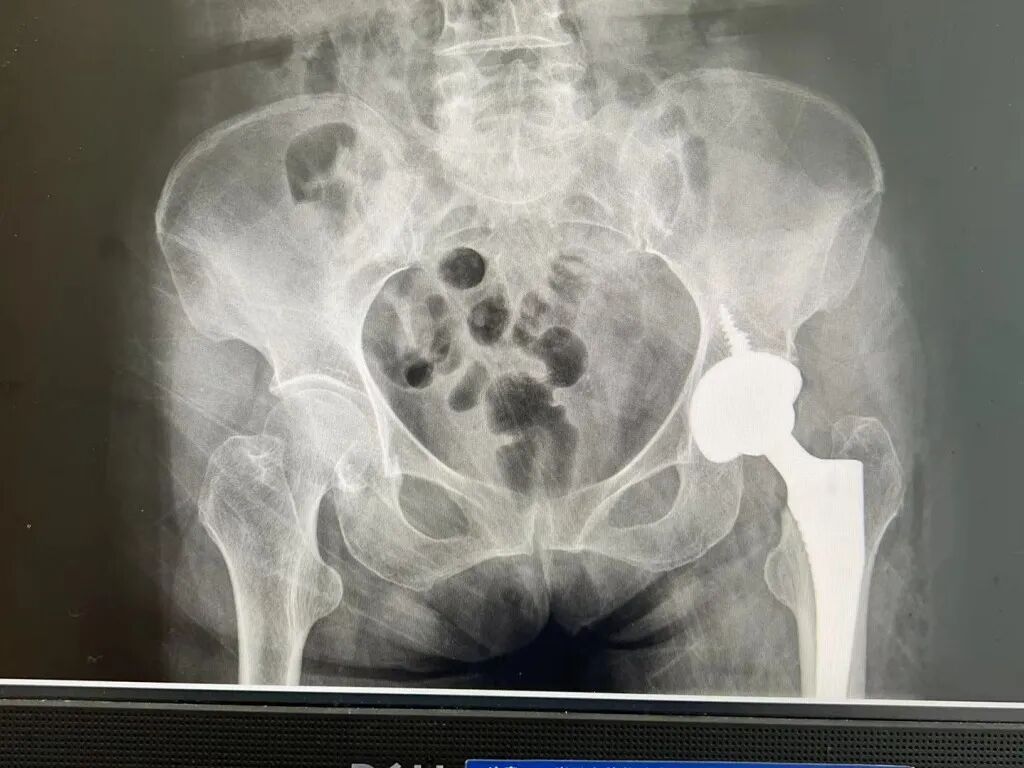

目前,VTS系统应用广泛,支持多种手术入路,在简单初次髋关节置换中,VTS系统精准辅助磨削让患者可以保留更多骨质,提高患者手术质量。在复杂髋关节置换中,VTS从规划到可视化假体植入再到可视化植钉追踪,全流程辅助提高了手术的安全性,让医生胸有成竹。

Visual Treatment Solution™(简称:VTS)是凭借医工交互进行术前规划与可视化实时监控的解决方案,旨在提升全髋关节置换术的手术性能和临床疗效。该系统将3D打印数字化制造技术与可视化智能辅助技术相结合,适应髋关节置换术中复杂的工作环境,从术前CT数据处理、3D手术规划,到术中的实时可视化追踪及髋臼假体植入等全流程进行辅助。